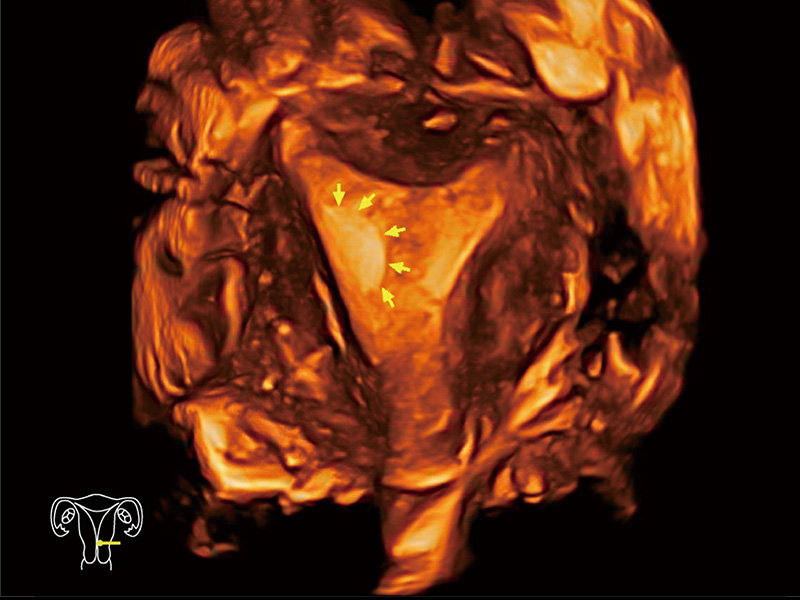

腔内三维成像技术获得显著提升,超大扇角在满足日常基础扫查的同时,支持卵泡自动测量及多种三维渲染模式,为您提供更多的诊断信息,尤其是在子宫畸形的诊断,内膜及肿瘤占位观测中起到了重要的作用。

单角子宫

子宫内膜息肉